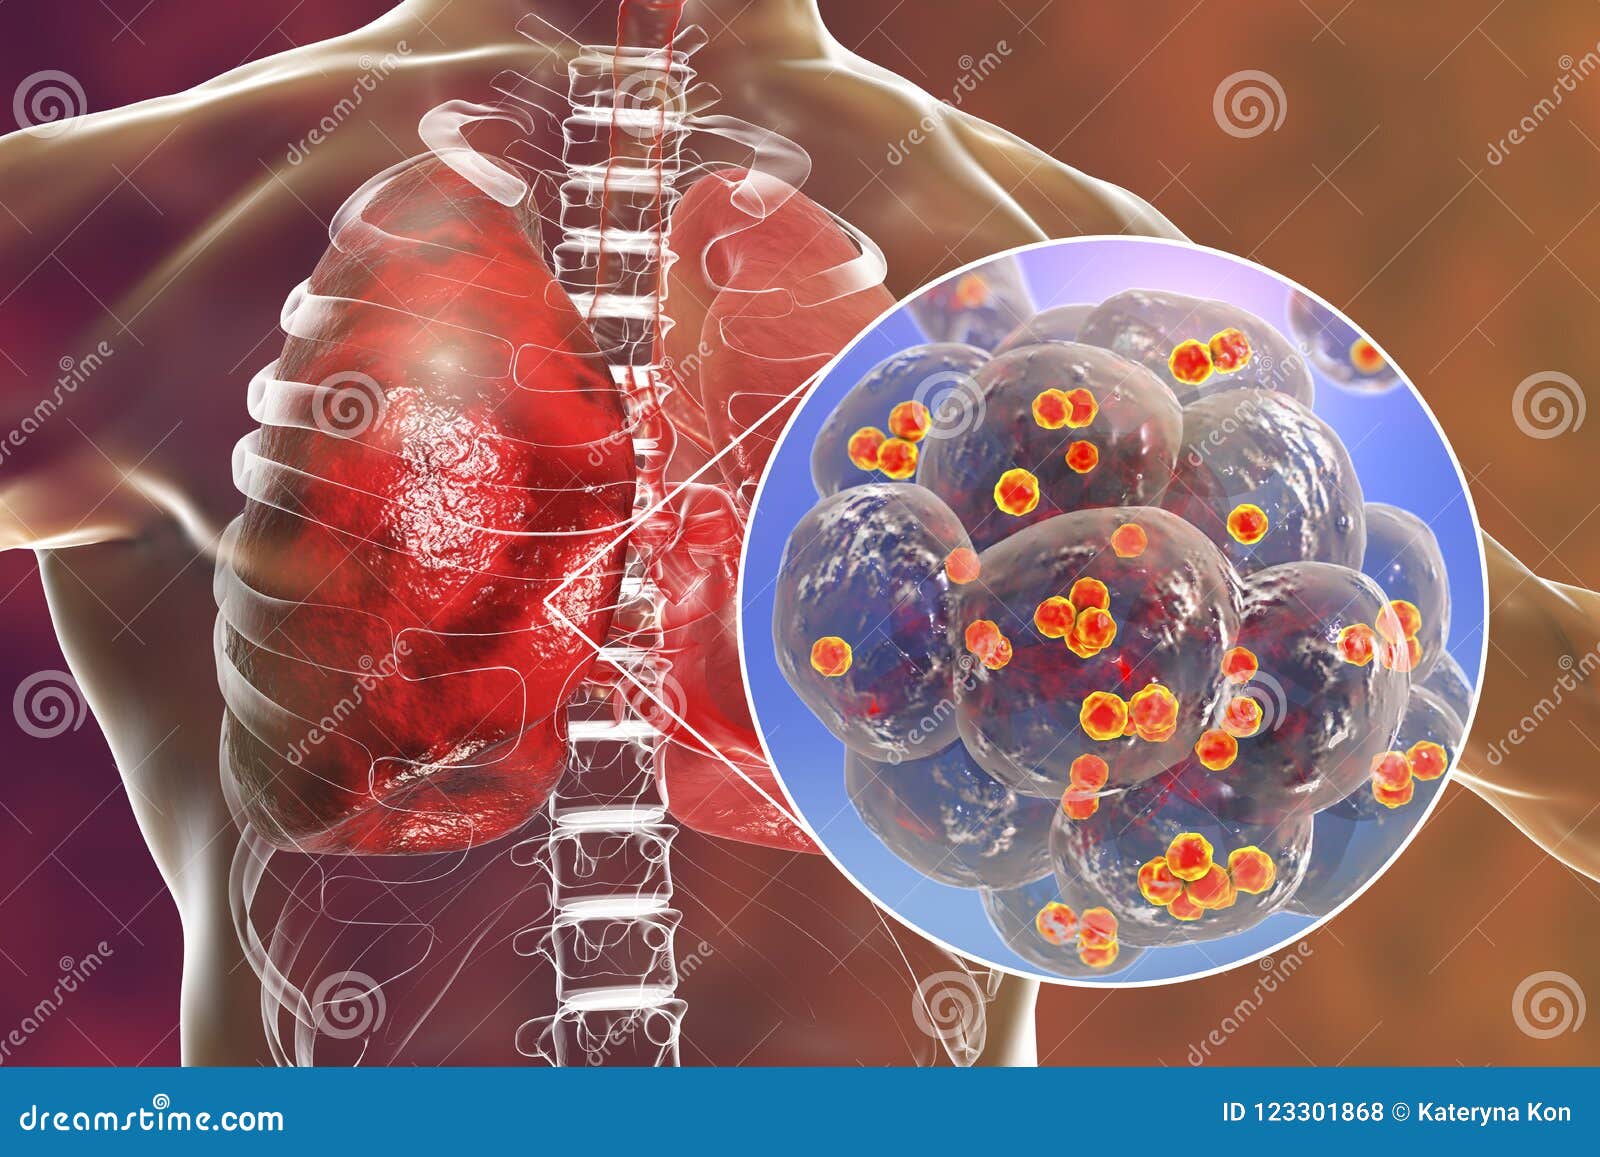

Фотографии бактерий, вызывающих бактериальные пневмонии у животных

Раздел: Другие животные